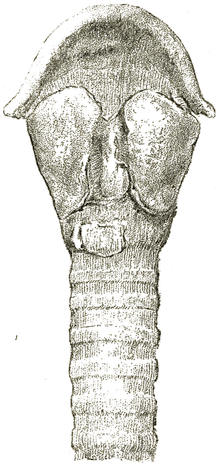

| Medico-Legal Consideration of Death by Mechanical Suffocation. D. S. Lamb, | 705 |